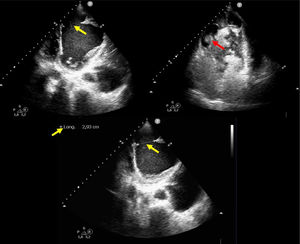

Presentamos el caso de una paciente de 61años con infarto de miocardio evolucionado hace un mes, que presentó complicaciones mecánicas postinfarto. La ecocardiografía evidenció un pseudoaneurisma apical de gran tamaño (fig. 1 y fig. 3: fecha azul) (Vídeo Anexo 1), con cuello de 2,93cm (fig. 1 y fig. 2: flecha amarilla) y paso de ecocontraste libre a su través (fig. 2: fecha roja), con la luz parcialmente trombosada (fig. 1 y fig. 3: fecha blanca). Se observó también un ventrículo izquierdo severamente dilatado y disfunción sistólica global muy severa (fig. 1) (FEVI 11%, IVT TSVI 7cm). A las 48horas de ingreso la paciente desarrolló shock cardiogénico SCAIC-D, que requirió soporte mecánico con ECMOV-A y balón de contrapulsación intraaórtico, logrando una notable mejoría de la perfusión orgánica. Tras coordinación con el hospital de referencia, fue trasplantada cardiaca código0, con una recuperación favorable. Este caso destaca la importancia del diagnóstico ecocardiográfico y el manejo con soporte mecánico en situaciones críticas de shock cardiogénico.